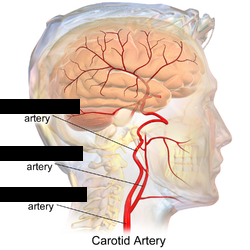

Internal/external/common carotid artery